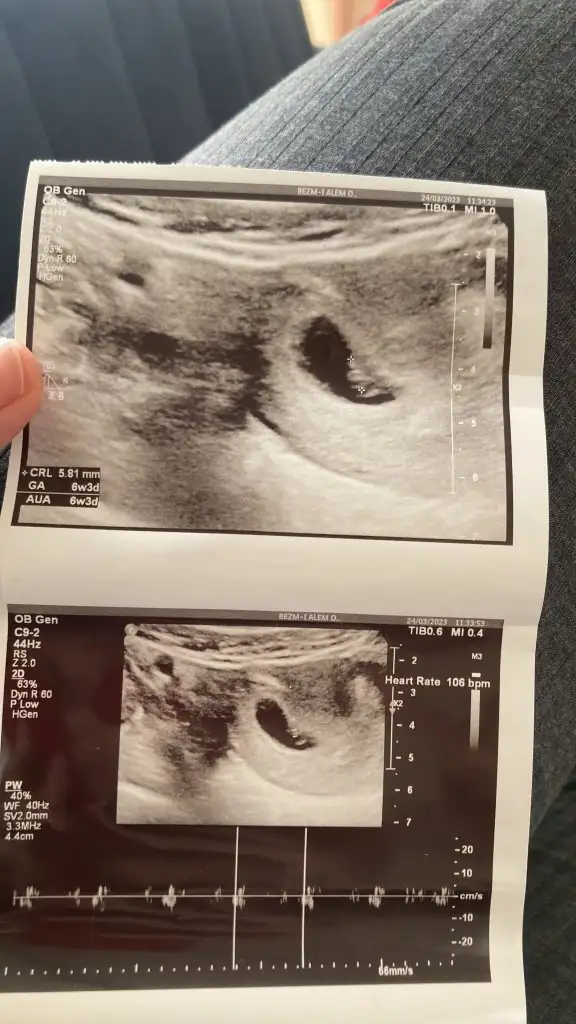

7+4 bana da tahminde bulunurmusunuz acaba7-8 haftaşık ultrason resmi varsa iyi tahmin yaparım

Görseli atın yaparım tabi7+4 bana da tahminde bulunurmusunuz acaba

Daha çok küçük dedi 2 haftaya anca belli olurmuş, 11 hafta 4 günlüktü gittiğimde elleri ayakları başı belirgindi ve ayaklarını oynatıyor, ama 7 haftalık ultrasonda hiçbir şeyi belirgin değildi ona görede bi teori yokmu, çünkü kızlarin buçuğu erkeğe göre daha geç oluşurmuşBurayada yaz bir şey söylerse eğer